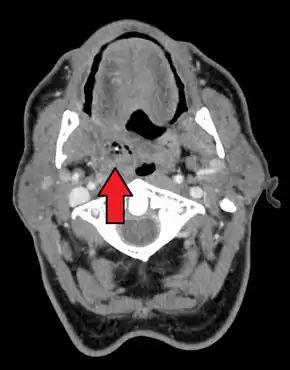

Right sided peritonsillar abscess

Peritonsillar abscess on the person's right as seen on CT imaging

Diagnosis is usually based on the symptoms.[1] Medical imaging may be done to rule out complications.[1] Medical imaging may include CT scan, MRI, or ultrasound is also useful in diagnosis.[1]